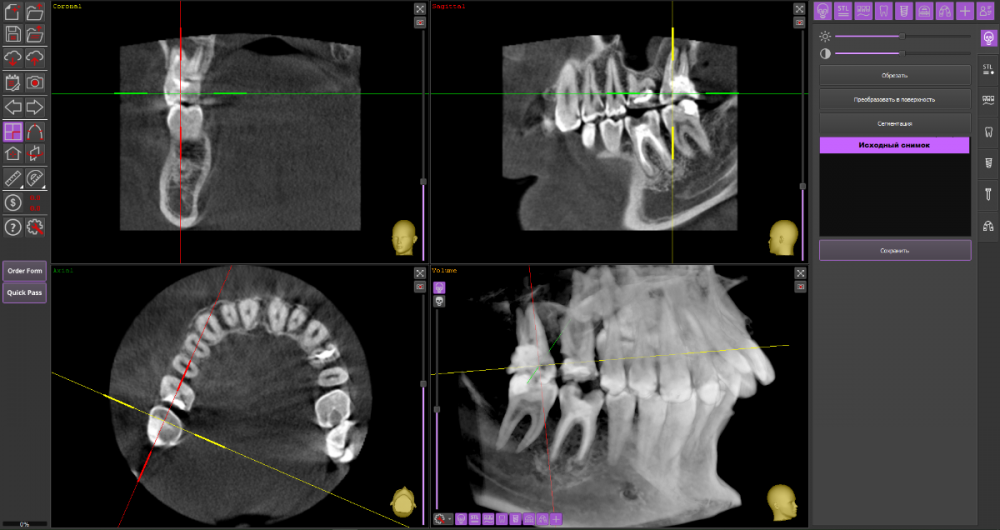

Добрый вечер, уважаемые специалисты. Подскажите, пожалуйста, есть ли возможность избежать удаления верхней 6-ки справа и использовать культевую вкладку + коронку для протезирования? Заранее спасибо за ответы. КТ: https://drive.google.com/drive/folders/17DOY2HNbp9x-5vxpit8V9hBL8D88hrAt?usp=sharing

На мой взгляд, зуб 16 вполне можно сохранить при условии адекватного лечения корневых каналов.

А вот зуб 17 перелечить маловероятно.

Я бы провел ревизию обоих зубов и далее уже смотрел что модно сохранить

после грамотной ревизии, как правило, не остаётся вопросов